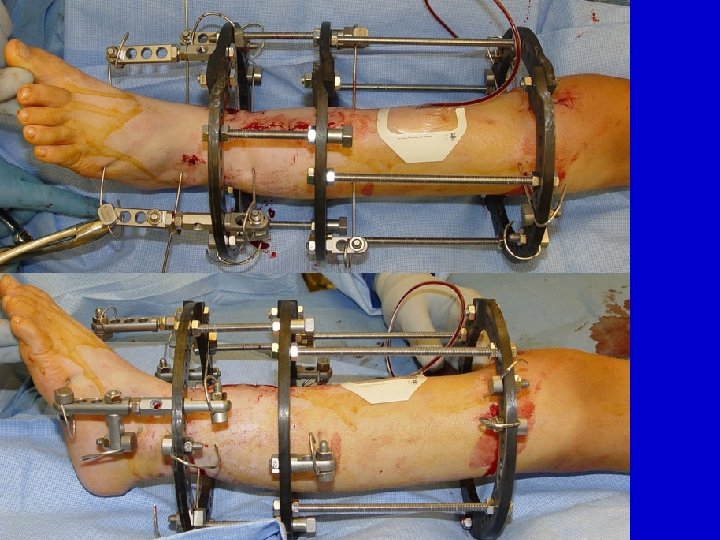

CPT resection